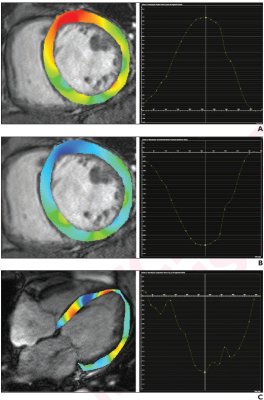

80-year-old patient with nonischemic dilated cardiomyopathy. Ejection fraction was 25.2%. Patient underwent cardiac MRI. A. Radial strain overlay on short-axis cine image and corresponding graph show global radial strain measurement, yielding value of 10.8%. B. Circumferential strain overlay on short-axis cine image and graph show global circumscribed strain measurement, yielding value of -8.5%. C. Longitudinal strain overlay on 4-chamber cine image and graph show global longitudinal strain measurement, yielding value of -10.7%. Global longitudinal strain measurement indicates lesser myocardial strain. Patient did not experience major adverse cardiovascular event after 3 years of follow-up.